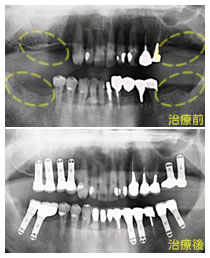

写真の上が、治療前の口腔内写真で、下がレントゲンです。

12本のインプラントを植立し、全額補綴処置をおこないました。臼歯部の咬合高径(咬み合わせの高さ)を上げて安定させました。